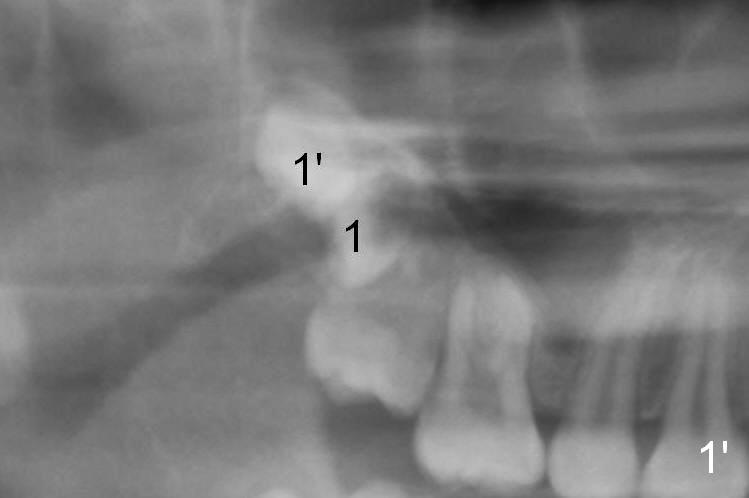

Now regarding this case.  No surgeon will take out wisdom teeth in a growing patient, which he is (the teeth anyway), without a current panx. So you are diagnosing from a weak position.  Regardless, you can see he has two #1 teeth--supernumerary.  It is clear the lower molars are mesial angularly impacted, with no hope of full eruption.  The upper wisdom teeth are still positioned high above the CEJ of the second molars, making removal difficult and traumatic.  But this is an old X-ray and we cannot make judgments because we know the roots are longer and the upper teeth have probably migrated more coronally.

Panoramic X-ray is taken immediately post extraction of one of the upper right 3rd molars (Fig.3,3') and 20 months postop (Fi.4,4').  In fact the remaining one has erupted normally.